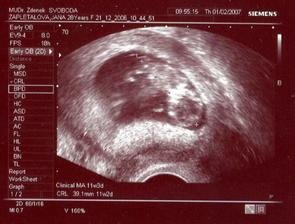

Tomášek se narodil přesně 3 týdny před termínem v Plzni na Slovanech 30.7.2007 Měřil 50 cm a vážil 2900g